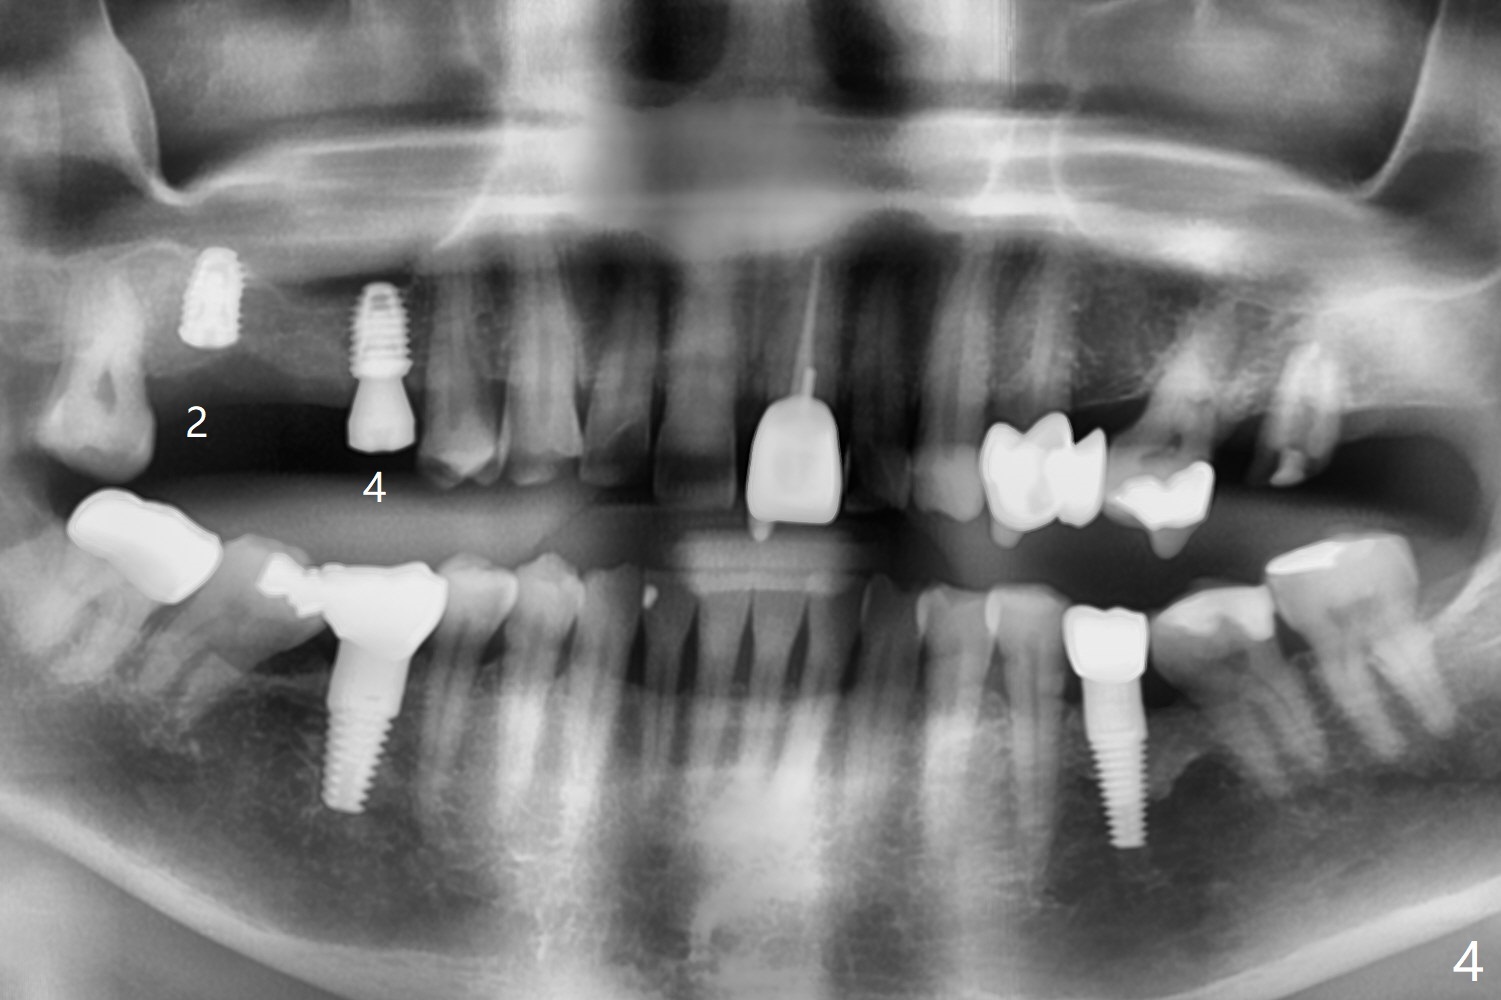

Eight months post socket preservation, the bone density at #2 feels low during osteotomy.  The site is underprep not only in depth, but also in diameter (4.0x7.3 mm with 10.5 mm offset), but a 5x7.3 mm implant is ~ 1 mm shy of the purposed depth.  Following 4.5x7.3 and 4.0x8.5 mm drills (without air leak), the implant reaches the depth, but with ~ 5 Ncm insertion torque (Fig.1).  Placement of the same sized implant at #4 (healed site) is smooth with satisfactory stability (~30 Ncm, Fig.2,3).  Ideally the site of #2 should have been prepared with sinus lift so that the apex of a longer implant would be engaged to the sinus floor for stability.  These two implants heal normally clinically and radiographically 1.5 months postop (Fig.4-6).  Bone surrounds the implant at #2 when it is uncovered 4 months postop (Fig.7).  The retainer at #4 looks short with large gingival embrasure (Fig.8 *) 6.5 months postop.  Finally the patient is ok with it because she does not like gingivectomy.  Provisional should have fabricated (Fig.9 light yellow curved lines) to create gingival scallops with secondary formation of papillae (arrows).